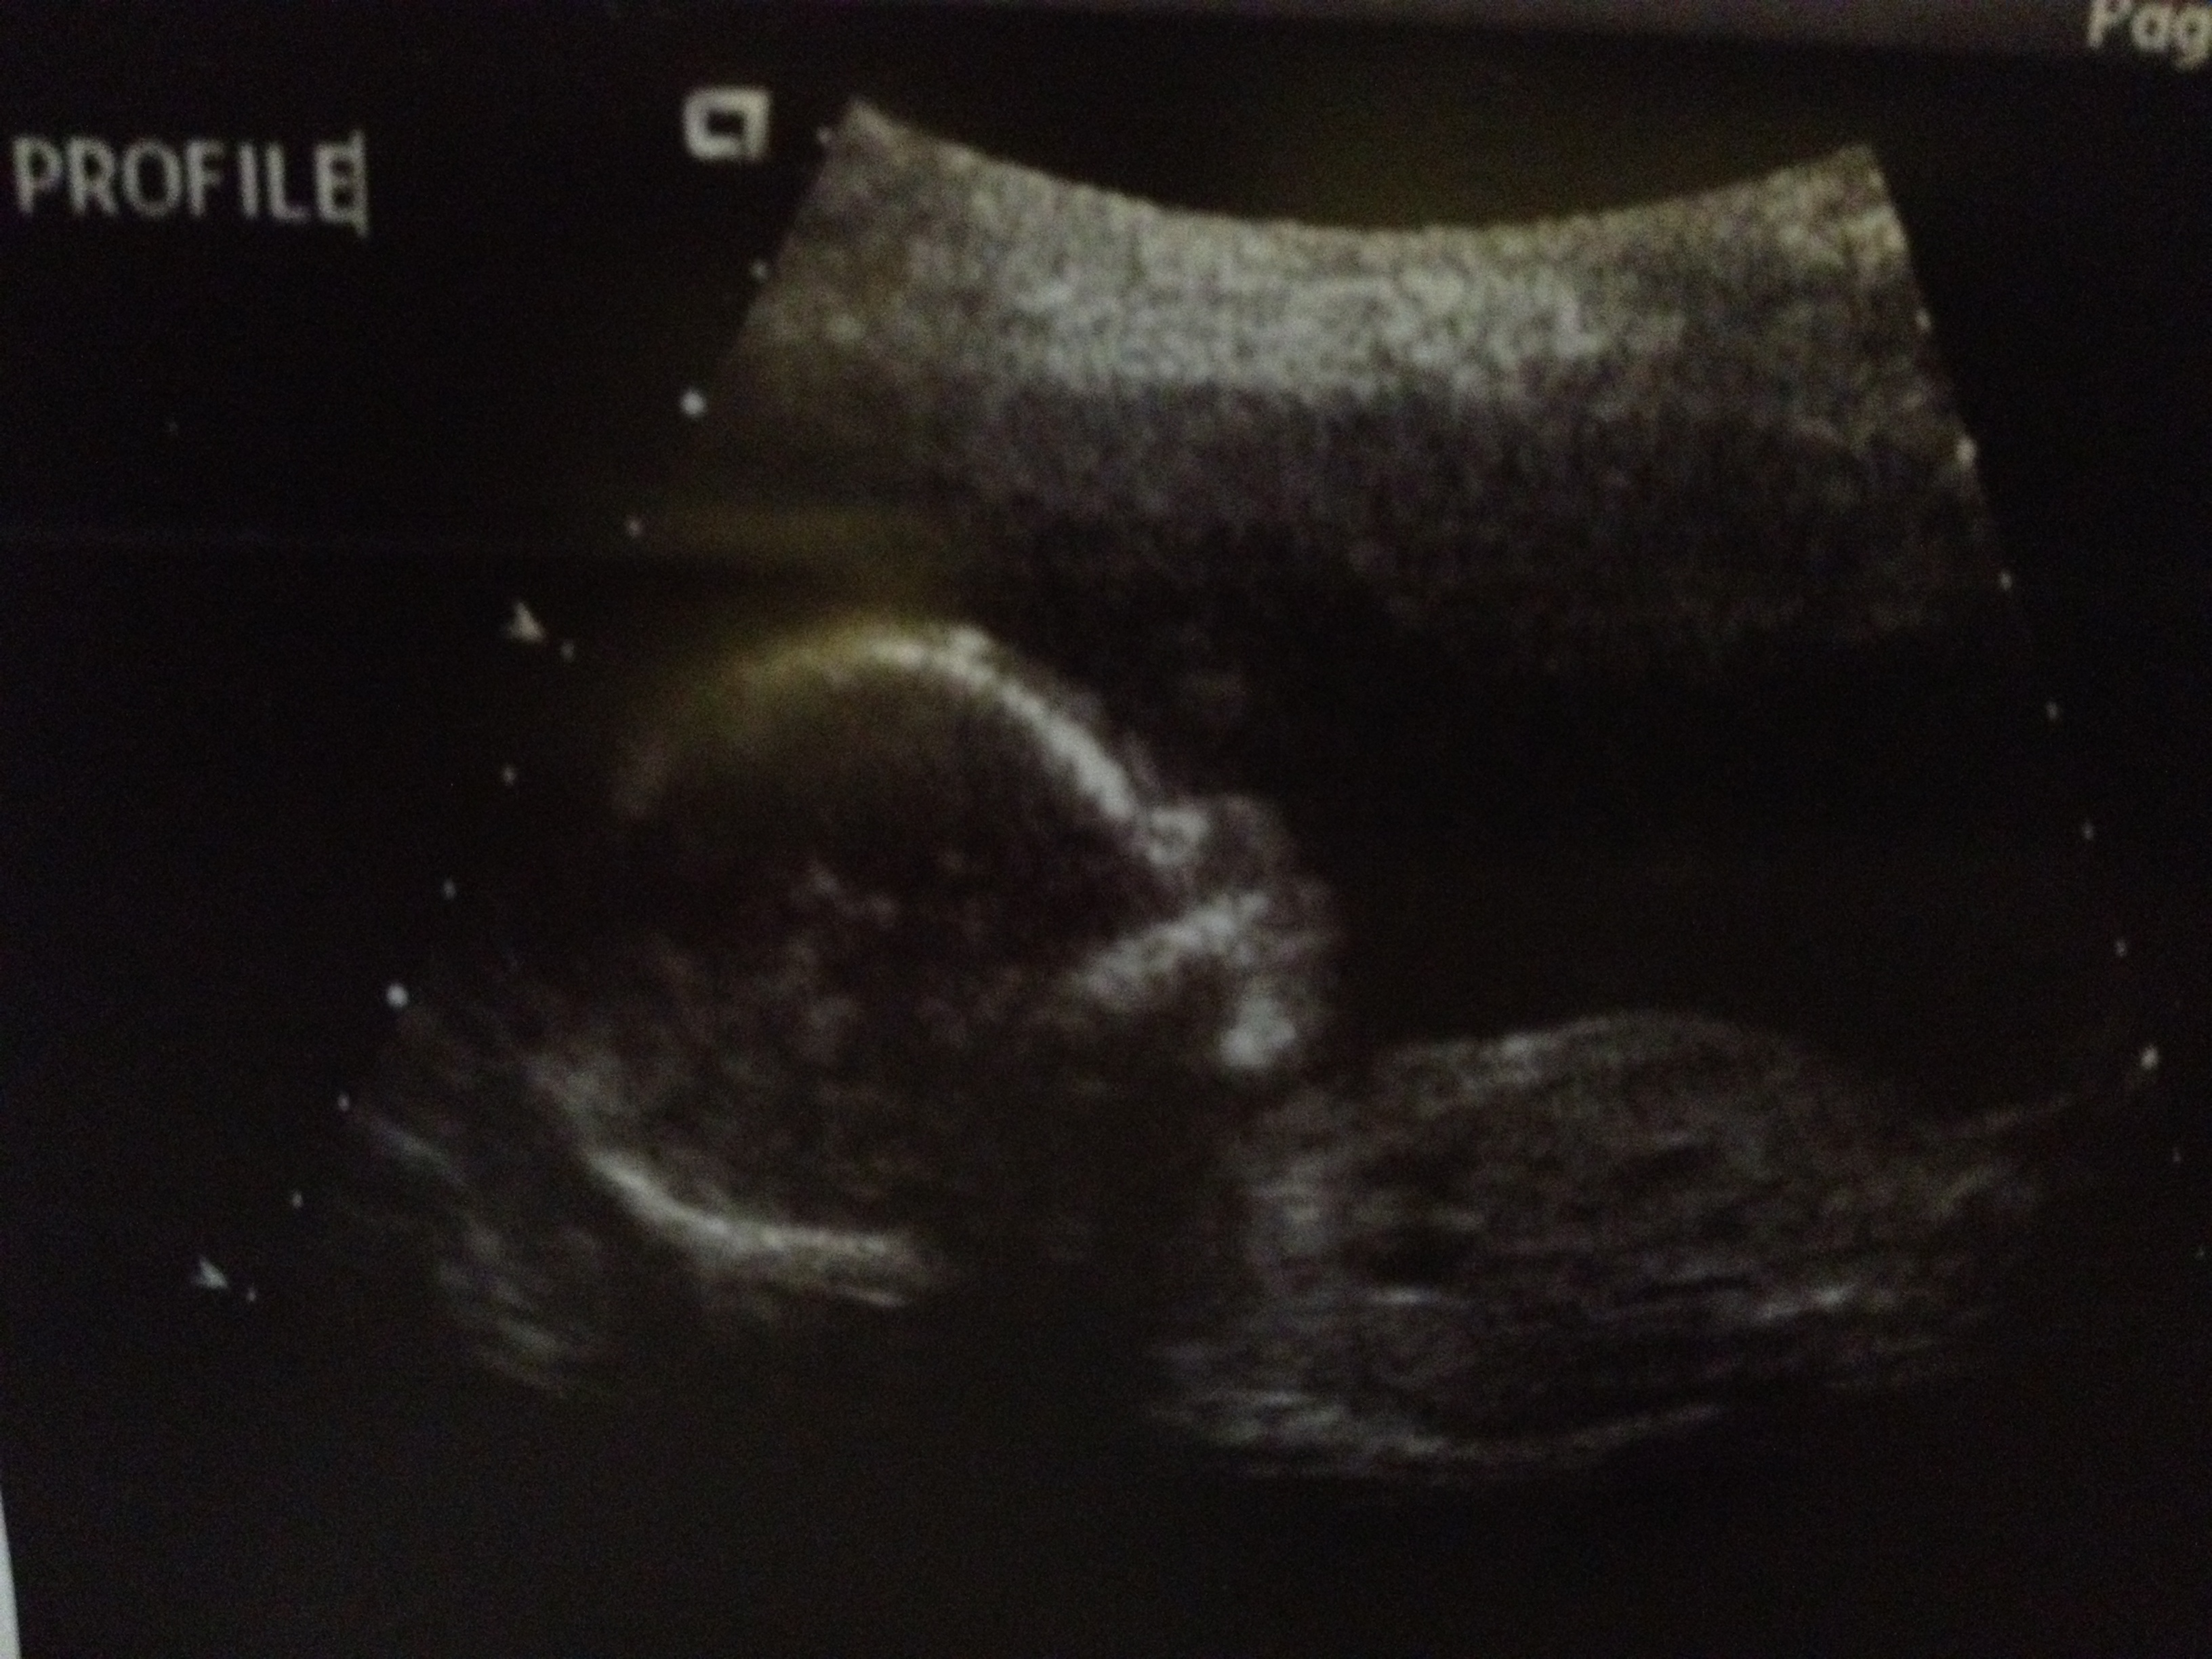

The fathers don’t get to go inside for the initial examination. So I sat in the waiting room with all the women for what seemed like an eternity (I’m sure it was like 5 minutes). The nurse came back and ushered me down a hall into a dimly-lit room. Jessica was on a special chair-bed thing with her shirt up off of her abdomen, which was greased up like a buttery dinner roll. The nurse said “Here we go” (Bud Light not included) and began operating the ultrasound. It took her about 5 seconds of adjustment until she settled on an image. She smiled and asked us “Do you know what that is?” On the screen was our answer: the stem on the apple, the spout on the teapot, the bo staff on our little ninja! “It’s a boy!” Jessica and I said together, trying not to yell.

The rest of the ultrasound was a blur. The nurse showed us our son’s brain, heart, spine, hands, feet, and even his little pouty face. I caught myself several times saying “Look at HIS hand” or “That’s HIS foot.” HIS. OUR SON. The feeling was beyond belief. The nurse printed out a strip of images for us, congratulated us, and sent us on our way. As we passed through the door into the waiting room, our family members let out a collective shriek (oh, ladies). My mom snapped photos, my sister clapped, and they all had giant smiles and looks of anticipation. But Jessica and I had a plan as to how we would reveal the news!